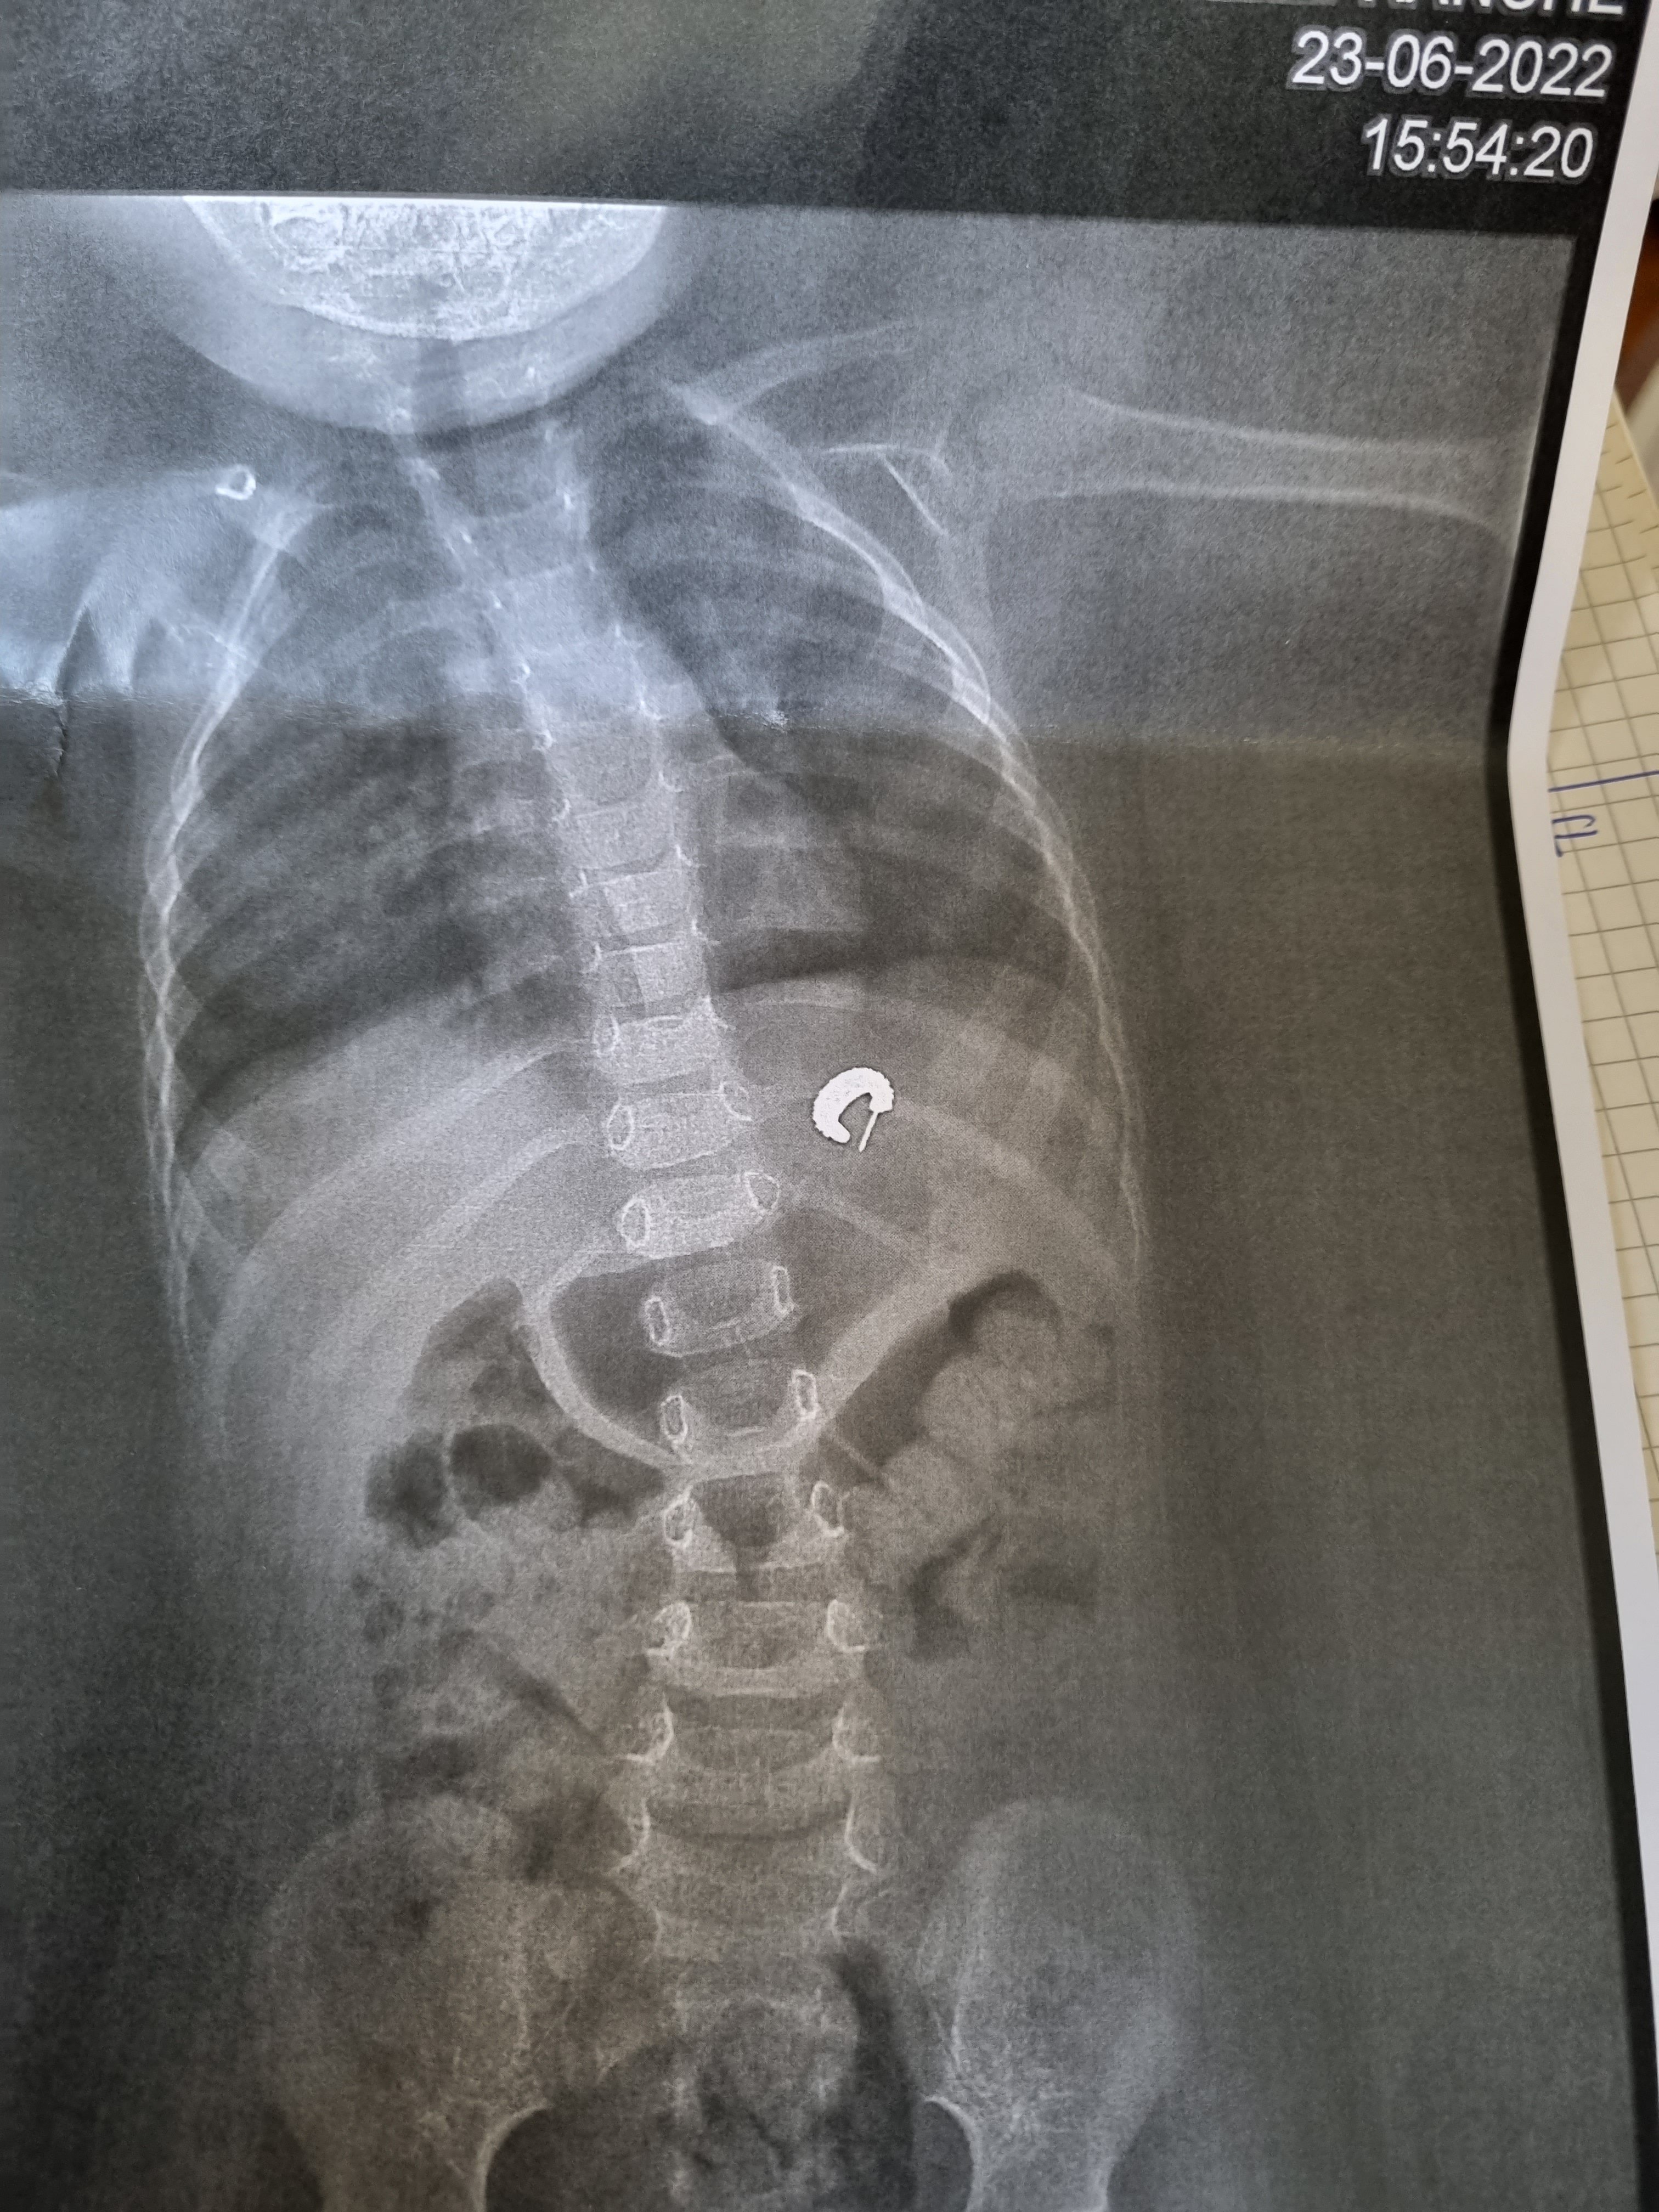

Journée pas mal hier, je sors du resto après deux dijos, pret pour retourner bosser. Je reçois un message de ma sdp qui me dit de rentrer en urgence, n°3 s'étouffe il a avalé quelque chose au moment ou elle le mettait à la sieste. C'était sa boucle d'oreille....

c'était la question en suspend hier aprem à l'hopital, ils hésitaient à "l'aspirer", et suite à plusieurs avis de médecin, le risque est faible vu que c'est dans l'estomac, mais à surveiller pendant 2 à 3 jours. Je t'avoue je ne suis toujours pas serein.

Et visiblement c'est moins dangereux qu'il évacue seul. Il a passé le plus risqué en tout cas

il va probablement rester sous surveillance médicale, et surveillance des selles pour retrouver l objet.